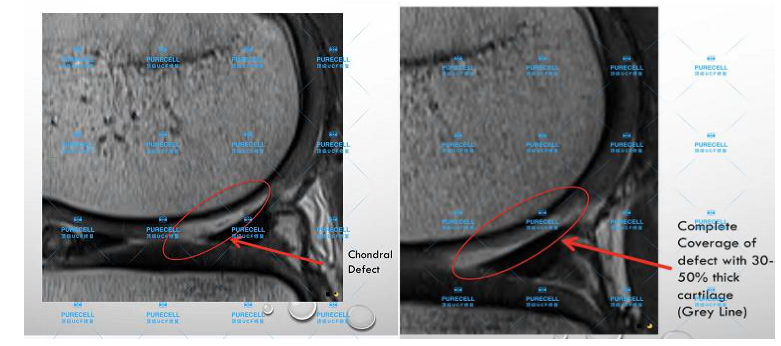

隨後Dr. Ian chinsee給大家正式介紹UCF抗衰老技術的原理及對膝關節部位的臨床對比,讓在場嘉賓更直觀的瞭解UCF膝關節修復的真實效果。

PURECELL首席科學家以及運動醫療專家已經驗證了UCF對膝關節修復的有效性,下圖是UCF軟骨及半月板修復前後影像對比。